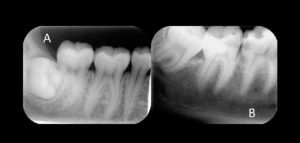

132 – Tratamiento de la reabsorción radicular interna idiopática perforante: controles radiográficos

La reabsorción radicular interna (RRI) es una afección inflamatoria que resulta en la destrucción progresiva de la dentina intra-radicular a lo largo de los tercios